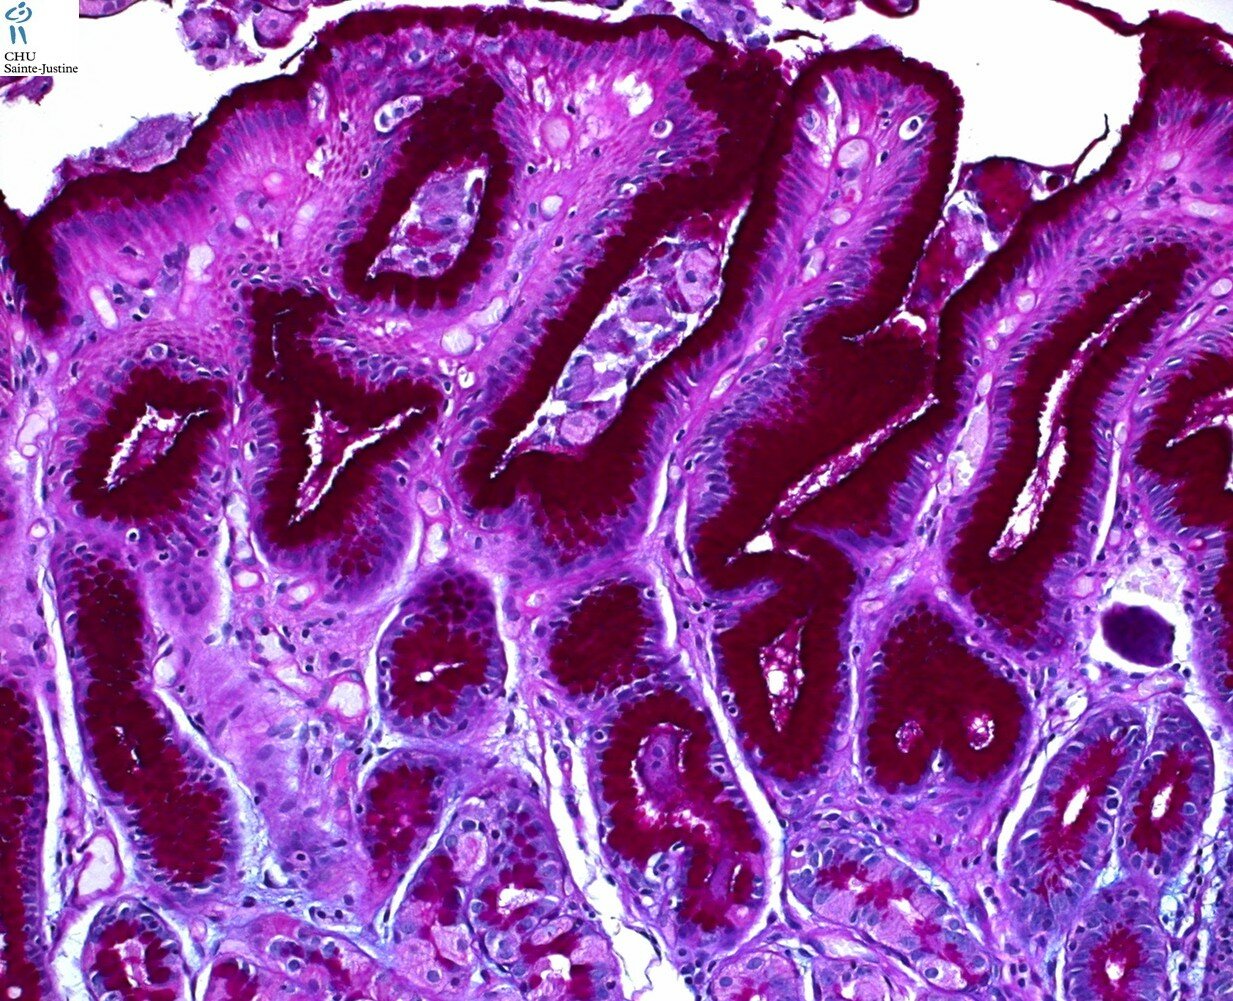

intestinal metaplasia in stomach